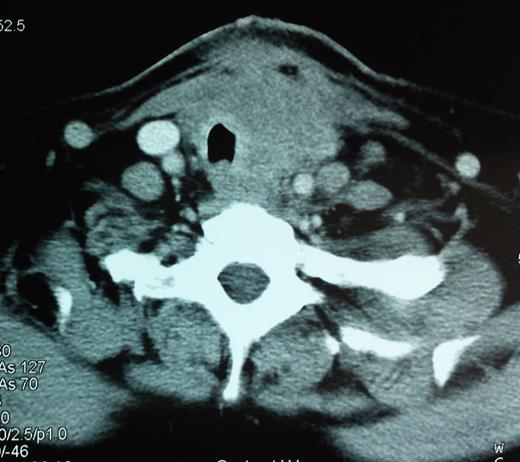

A CT scan showing a 6.2-cm mass pressuring and infiltrating the trachea and surrounding soft tissue.